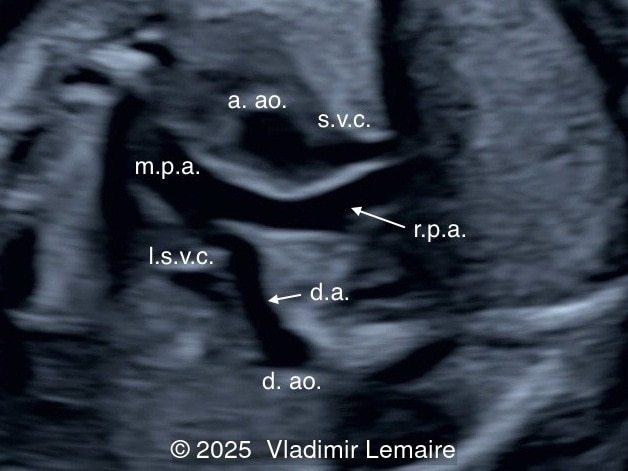

We present a case of isolated tricuspid atresia type 1 with persistent left superior vena cava. No other extracardiac anomalies were found. Our diagnosis was confirmed after birth.

In the images below, the abbreviations are as follows: RA: right atrium; RV: right ventricle; LV: left ventricle; MV: mitral valve; LA: left atrium; FO: foramen ovale; SVC: superior vena cava; LSVC: left superior vena cava; PV: pulmonary veins; PA: pulmonary artery; MPA: main pulmonary artery; RPA: right pulmonary artery; AO: aorta; dAO: descending aorta; aAO: ascending aorta; DA: ductus arteriosus; T: trachea; * marks the ventricular septal defect.

The size of the great vessel arising from the right ventricle should be evaluated for the presence of stenosis, which is a common association. The severity of right outflow tract obstruction directly correlates with the size of the right ventricle and the ventricular septal defect. Occasionally, pulmonary or aortic atresia can be found.

Flow across the ductus arteriosus is usually antegrade. The demonstration of retrograde flow in the arterial duct is a sign of ductal-dependent pulmonary circulation with possible cyanosis in the newborn. Ductal-dependent pulmonary circulation in tricuspid atresia is seen in severe pulmonary stenosis or atresia in association with a small right ventricle.

Associated cardiac findings include a large interatrial communication such as a patent foramen ovale or an atrial septal defect, transposition of the great arteries, and various degrees of ventricular outflow obstruction. Ventricular outflow obstruction can vary from patent pulmonary artery to stenosis and atresia, and from patent aortic arch to aortic stenosis, coarctation, or interruption of the aortic arch. Other associated cardiac lesions include persistent left superior vena cava as presented in this case, right aortic arch, pulmonary venous abnormalities, and juxtaposition of the atrial appendages. Extracardiac anomalies can be found in tricuspid atresia and there is a rare association with chromosomal aberration such as microdeletion 22q11. Fetal karyotyping should be offered.